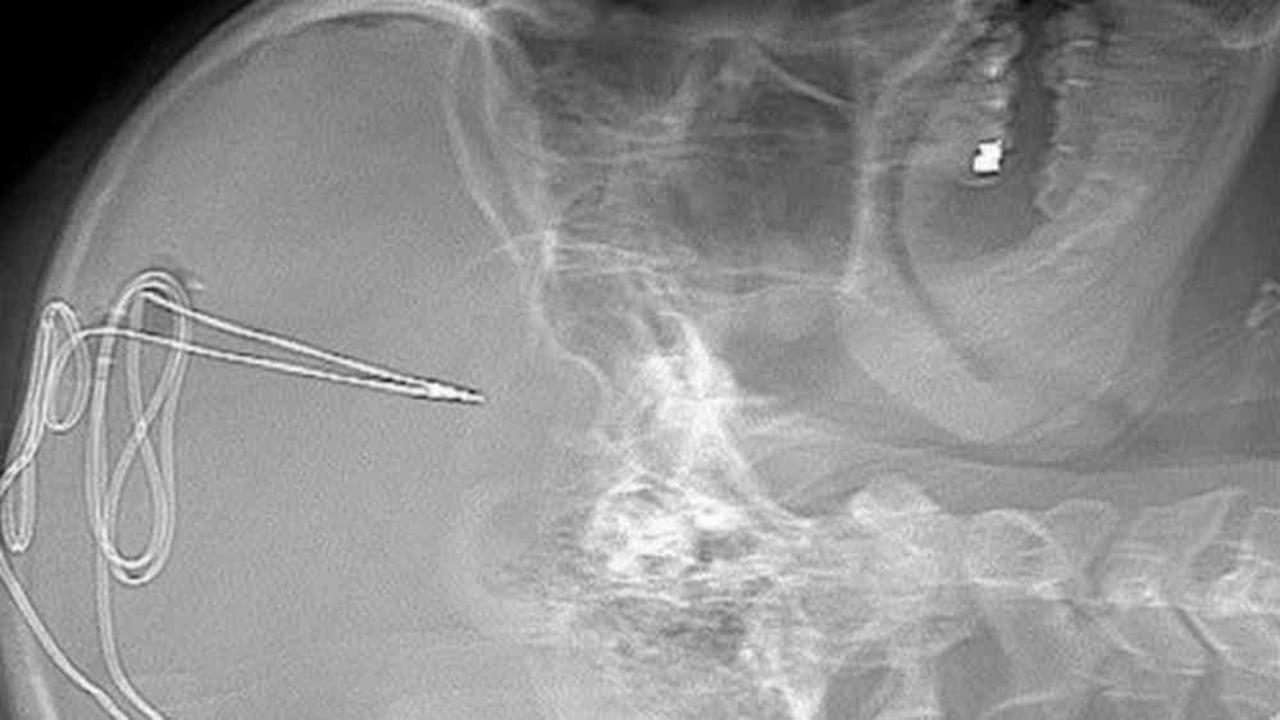

El proceso comienza con una serie de escáneres cerebrales. Después se practica la cirugía. Para ello se hace un pequeño agujero en el cráneo para insertar un electrodo de 1 milímetro en un área específica del cerebro que regula impulsos como la adicción y el autocontrol.

Se inserta una batería debajo de la clavícula, de manera que la actividad cerebral se monitorea de manera remota por el equipo de médicos, fisiólogos y expertos en adicción para ver si el anhelo de consumir la sustancia disminuye.